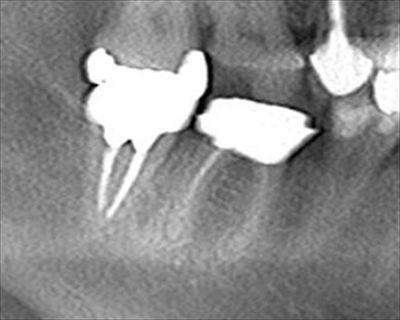

右下大臼歯2本の再根管治療を行いました。2018.05.24

右下第一大臼歯と第二大臼歯の金属を除去し、再根管治療を行います。

根管充填後に撮影したデンタルX線写真です。